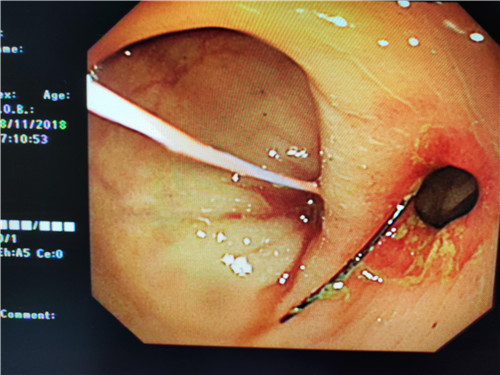

在检查过程中,当曹鹏主治医师将内镜进至吻合口狭窄处时,却偶然发现狭窄部位旁边还有一小小入口,探镜而入,发现这条小小隧道与狭窄部一同通向肠腔,中间相隔了一条不宽不窄的“桥梁”,把本来通畅的“大路”隔成了两条幽径小道,因此患者排便才会堵塞不通。经过反复观察,仔细斟酌后曹鹏医生萌生了,把“桥梁”拆掉,使“曲径小路”变“宽敞大道”的想法。因为这时如果按原计划行肠镜下吻合口扩张术已经没有太大的意义,但肠道薄弱容易造成穿孔,“桥梁”处是否有大的血管,存在出血、穿孔的风险等等,这些都需要与主管医生进一步探讨。随即他与普通外科史和平主任,消化内镜室王莹主任会诊后决定实施“粘膜桥离断术”(ESD内镜下粘膜剥离术)。将术中风险及意外向患者及家属充分告知后,征得患者家属同意签字,随后便开始施行手术。在史主任、王主任、李侠护士长的支持保驾护航之下,曹鹏医生以精湛的医疗技术,与护士的默契配合,顺利完成了手术,术中无出血、穿孔,眼前显示器屏幕上出现了预期中的“宽敞大道”,手术成功了!大家原本绷紧的面容出现了笑容。患者从此以后不会再有排便不畅的痛苦了,患者唐某及家属,欣喜及感激之情溢于言表,医生们再一次为他解决了一件大事情,患者术后恢复良好。